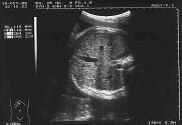

Bebeğiniz bu haftanın sonunda yaklaşık 950 gram olacak. Ancak sizin ve eşinizin yapısal özelliklerine göre bu 650 gram kadar düşük olabileceği gibi, 1500 gram kadar yüksek olabilir. İri bebek, ya da düşük kilolu bebek tanısı genelllikle seri ölçümlerle konur.Bu seri ölçümlerde bebeğin belli bir zaman dilimi içerisinde ne kadar kilo aldığı belirlenir. Yandaki ultrason resminde bebeğin karın çevresi kesitini görüyorsunuz. Hemen kalbin altından yapılan ve karaciğerin büyük kısmını içine alan bu kesit, gelişme geriliği tanısının konmasında çok önemlidir.